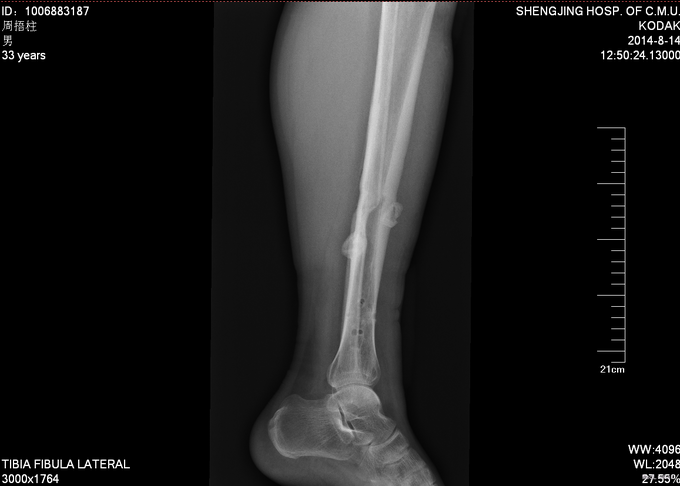

患者2012年8月发生车祸,致右股骨及左胫骨骨折,后于我院行右股骨骨折闭合复位内固定术,左胫骨骨折闭合复位内固定术,手术顺利,安返病房,术后康复锻炼,定期复查,近期复出X线,提示骨折愈合良好,今日门诊以“右股骨骨折,左胫骨骨折术后”为主要诊断收入我科

患者步入病房,神志清,右大腿压痛叩击痛(—),左小腿压痛叩击痛(—)。双下肢等长。双下肢感觉运动均正常。

入院后完善检查,查无手术禁忌症后右股骨干骨折术后内固定物取出术,左胫骨骨折术后内固定物出去术,术后第二天自动退院。